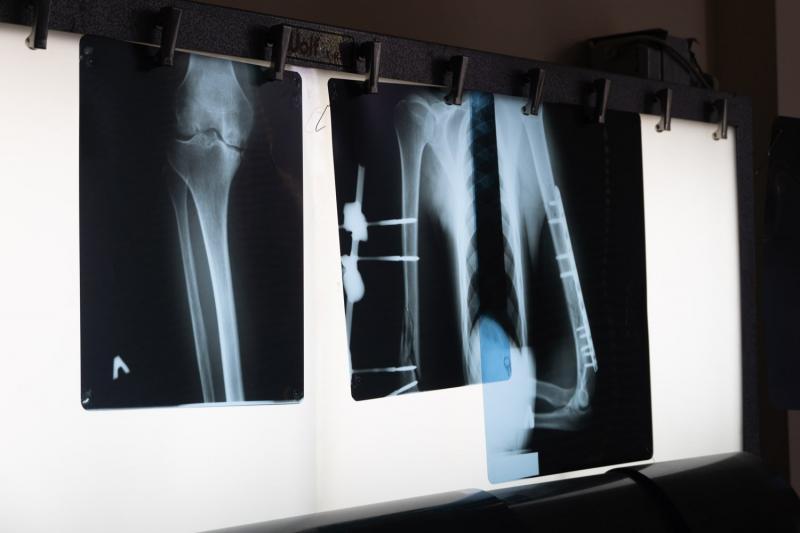

Коксартроз – поширене захворювання кульшових суглобів, що проявляється атрофією і поступовим руйнуванням суглобових хрящів. Патологія з часом призводить до порушення рухливості, сильних болів і зрештою –інвалідності. Щороку через цю хворобу інвалідність отримують близько 20 ужгородців, здебільшого це люди працездатного віку. Ендопротезування – так називають операції із заміни рідних суглобів штучними імплантами – повертає людям можливість рухатися, допомагає забути про нестерпний біль.

Ендопротезування – операція дорога, вона складається з ціни самого протеза (залежить від виду суглоба і матеріалу, з якого він зроблений), витратних матеріалів та реабілітації. Для багатьох хворих вартість життєво необхідної операції є непосильною.